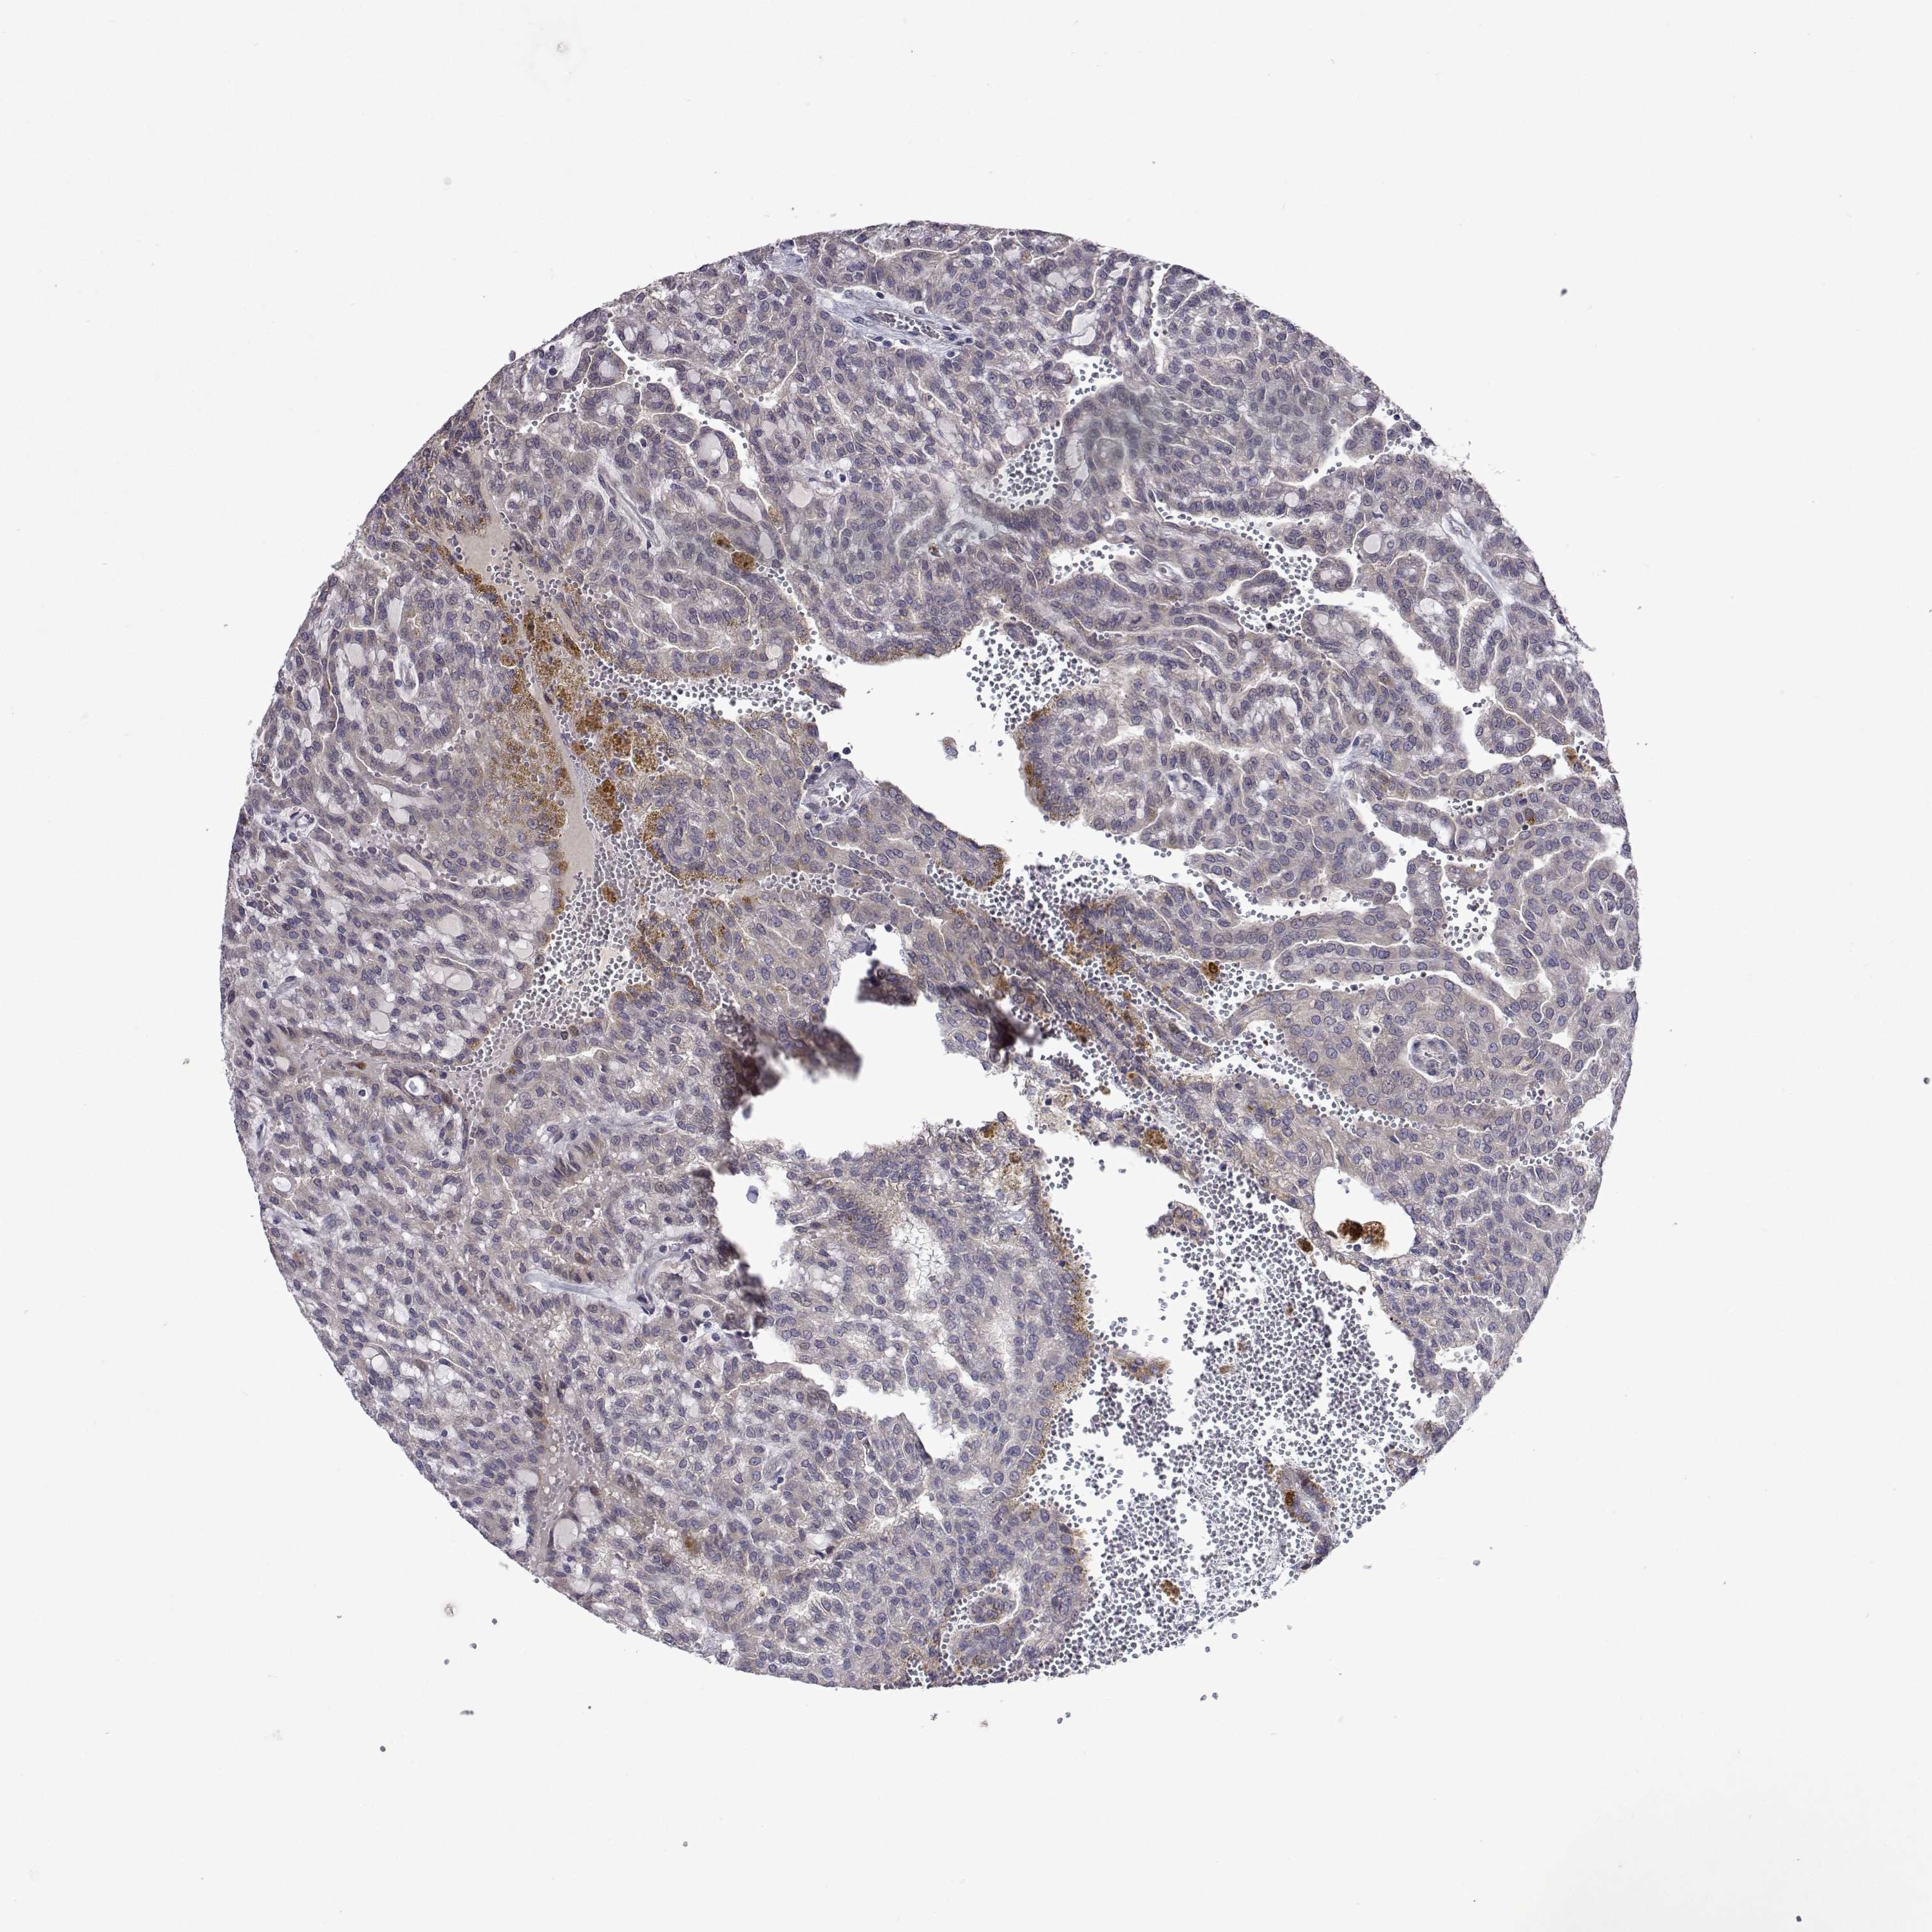

KIDNEY RENAL CLEAR CELL CARCINOMA (VALIDATION) - Interactive survival scatter ploti

The Survival Scatter plot shows the clinical status (i.e. dead or alive) for all individuals in the patient cohort, based on the same data that underlies the corresponding Kaplan-Meier plots. Patients that are alive at last time for follow-up are shown in blue and patients who have died during the study are shown in red.

The x-axis shows the expression levels (FPKM) of the investigated gene in the tumor tissue at the time of diagnosis. The y-axis shows the follow-up time after diagnosis (years). Both axes are complimented with kernel density curves demonstrating the data density over the axes. The top density plot shows the expression levels (FPKM) distribution among dead (red) and alive patients (blue). The right density plot shows the data density of the survived years of dead patients with high and low expression levels respectively, stratified using the cutoff indicated by the vertical dashed line through the Survival Scatter plot. This cutoff is automatically defined based on the FPKM cutoff that minimizes the p-score. The cutoff can be changed by dragging the vertical line or by entering a cutoff value in the square labeled "Current cut-off".

Under the Survival Scatter plot the p-score landscape (black curve; left axis) is shown together with dead median separation (red curve; right axis). Dead median separation is the difference in median mRNA expression between patients who have died with high and low expression, respectively. It is calculated as follows: median FPKM expression of dead patients with high expression - median FPKM expression of dead patients with low expression. This is intended to aid the user in visually exploring custom cutoffs and the associated p-scores and dead median separation.

Individual patient data is displayed and can be filtered by clicking on one or more of the category buttons on the top of the page. Categories describing expression level and patient information include: high, low, alive, dead, female, male and tumor stages. The scale of the x-axis can be toggled between linear and log-scale by clicking on the "x log" button. Mouse-over function shows TCGA ID, patient information and mRNA expression (FPKM) for each patient.

& Survival analysisi

Kaplan-Meier plots summarize results from analysis of correlation between mRNA expression level and patient survival. Patients were divided based on level of expression into one of the two groups "low" (under cut off) or "high" (over cut off). X-axis shows time for survival (years) and y-axis shows the probability of survival, where 1.0 corresponds to 100 percent.

TARBP2 is validated prognostic, high expression is unfavorable in Kidney Renal Clear Cell Carcinoma (validation)

Best expression cut offi

Based on the FPKM value of each gene, patients were classified into two groups and association between prognosis (survival) and gene expression (FPKM) was examined. The best expression cut-off refers the FPKM value that yields maximal difference with regard to survival between the two groups at the lowest log-rank P-value. Best expression cut-off was selected based on survival analysis .

When clicking on this number, the vertical dashed line indicating cut-off, the interactive survival plot, and the Kaplan-Meier curve will be adjusted to show results based on the best expression cut-off.

: 11.85

TCGA RNA samplesi

RNA-seq data is reported as average FPKM (number Fragments Per Kilobase of exon per Million reads), generated by the The Cancer Genome Atlas (TCGA) .

Normal distribution across the dataset is visualized with box plots, shown as median and 25th and 75th percentiles. Points are displayed as outliers if they are above or below 1.5 times the interquartile range. FPKM values of the individual samples are presented next to the box plot.

Average pTPM 13.3

Number of samples 100